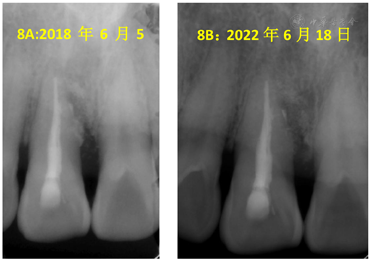

11完善治疗后3个月、半年、四年半复查,11均无不适,叩痛(-),不松,牙龈未见明显红肿等,PD2~4 mm。x线片均显示11近中骨质恢复良好。

11根管充填后3个月、半年、四年半复查,11均无不适,叩痛(-),不松,牙龈未见明显红肿等,PD 2~4 mm。x线片均显示11近中骨质恢复良好。在随访的四年半,牙周维护依靠患者自行的口腔卫生维护,均未再进行任何牙周治疗。

刘学军教授认为当牙根纵裂诊断确立后,应尽早拔牙或截除患根,以保存骨量进一步行种植、修复治疗。很多试图修复裂隙的措施都难以期待远期疗效,且增加骨缺损风险[1]。但因患者保留该牙意愿强烈,我们仍尝试进行治疗。该牙为上颌中切牙,无法像磨牙一样只截除患根保留剩余牙根。且其隐裂位置在根中部,无法行根尖手术截除根下段,否则剩余牙根太短预后不佳。受冠部隐裂磨除隐裂纹充填树脂的治疗方案启发,我们尝试快机磨除隐裂后充填生物相容性良好的MTA,植骨粉后缝合。该患者经过治疗后效果良好,骨质恢复,根管治疗术后3个月、半年、4年半复查均无异常。该案例通过根管治疗结合牙周翻瓣去除感染及裂隙备洞充填和植骨,成功地解决了根尖牙周联合性感染的治疗难题,为以后不完全根裂的治疗提供了案例支持。